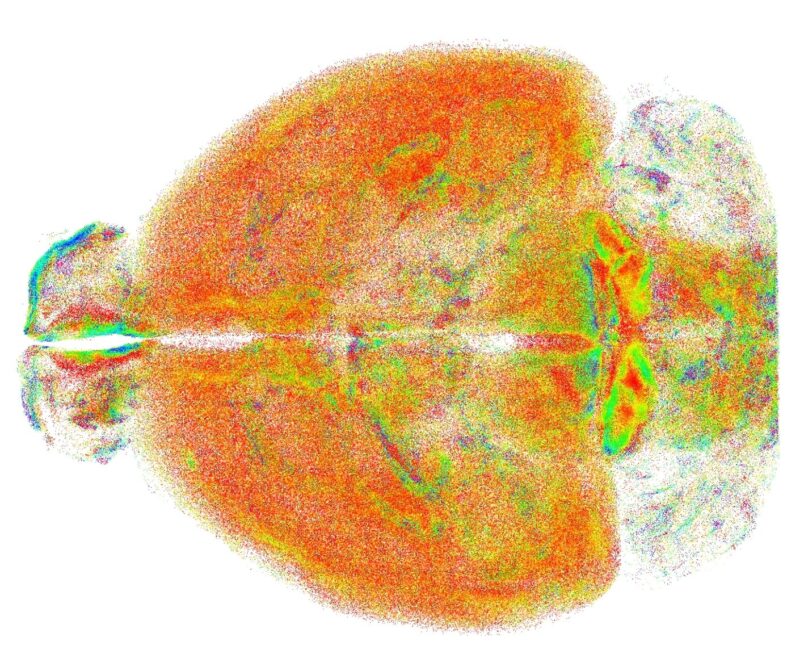

La nuova tecnica elaborata dai ricercatori, chiamata RAPID (acronimo di Rapid Autofocus via Pupil-split Image phase Detection) propone una nuova integrazione della microscopia a foglio di luce, capace di correggere in tempo reale i disallineamenti introdotti dal campione, consentendo di visualizzare e rappresentare interi cervelli di modelli murini con risoluzione subcellulare.

L'alta risoluzione garantita da RAPID – che è anche oggetto di un brevetto internazionale di cui sono titolari Unifi, Lens e Cnr - ha permesso ai ricercatori di studiare su scala dell'intero cervello problematiche finora analizzate solo in piccole aree circoscritte. Si è indagata, ad esempio, la distribuzione spaziale di un particolare tipo di neuroni – che esprimono somatostatina – mostrando come queste cellule tendono ad organizzarsi in cluster spaziali, che si sospetta rendano più efficace la loro azione inibitoria.

Un'altra applicazione riguarda la microglia, un insieme di cellule con diverse funzioni (dalla risposta ad elementi patogeni alla regolazione della plasticità dei neuroni), la cui forma cambia a seconda del ruolo che svolgono. L'analisi della microglia effettuata con RAPID ha evidenziato differenze significative tra varie regioni del cervello, aprendo la strada a nuovi studi sul ruolo di questa popolazione cellulare.